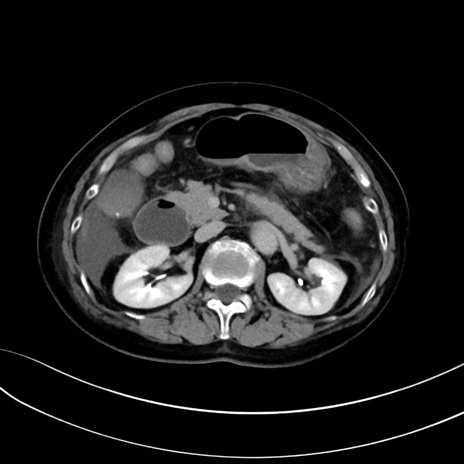

症例13 CT(横断像)1日半後